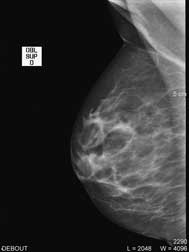

| Debout, le sein légèrement comprimé, deux clichés sont réalisés de face et en oblique sur chaque coté ; d’autres clichés localisés pour mieux analyser une zone peuvent aussi être effectués. |